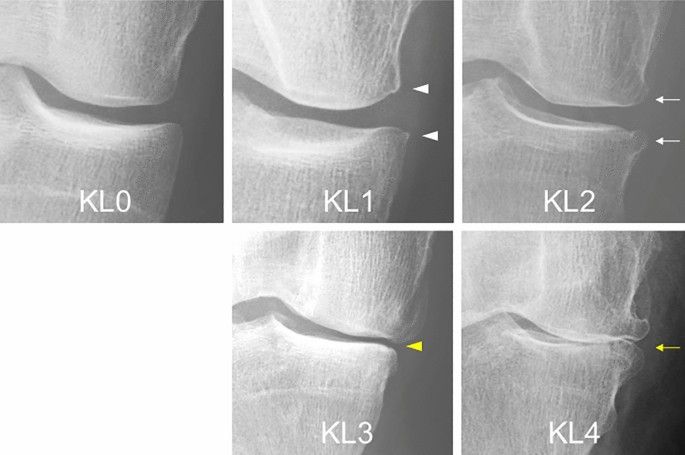

Radiografías convencionales

- Son la prueba de imagen estándar inicial.

- Permiten evaluar el estrechamiento del espacio articular, osteofitos, esclerosis subcondral y deformidades óseas que son típicas de la artrosis. elsevier.es

- El grado de artrosis en las radiografías se clasifica frecuentemente mediante la escala de Kellgren y Lawrence.

- No siempre existe una correlación directa entre hallazgos radiográficos y la intensidad del dolor o síntomas clínicos, por lo que deben interpretarse junto con la clínica del paciente. Madrid